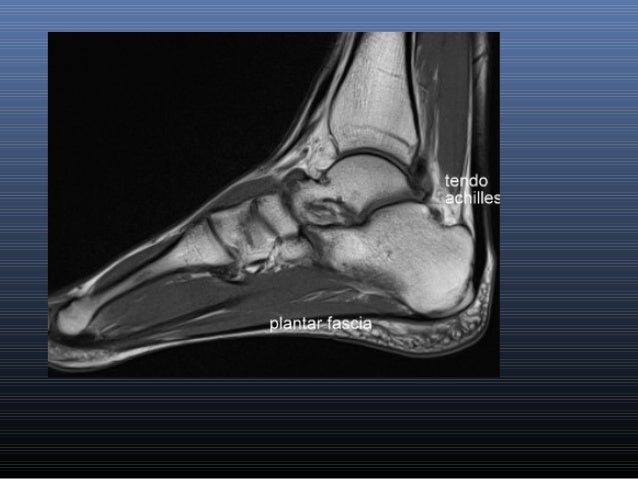

Foot Muscles Mri : A 44-year-old man with right ankle pain and weakness

Foot Muscles Mri : A 44-year-old man with right ankle pain and weakness. Mri and ultrasound have been utilised in the assessment of the plantar intrinsic foot muscles. Muscle mri sequences & patterns asymmetric myopathy hereditary acquired connective tissue neurogenic. .magnetic resonance imaging (mri) or ultrasound imaging (usi) (soysa et al., 2012; The muscles acting on the foot span from above the knee to various points on the foot skeleton. Indications for foot mri scan.

The flexor digiti minimi brevis (flexor brevis minimi digiti, flexor digiti quinti brevis) lies under the metatarsal bone on the little toe, and resembles one of the interossei. In addition, an image of all the muscles of the back and. Mri with hardware in foot? .magnetic resonance imaging (mri) or ultrasound imaging (usi) (soysa et al., 2012; Magnetic resonance imaging (mri), with its multiplanar capabilities, superior soft tissue contrast, excellent spatial resolution, ability to image bone marrow, noninvasiveness, and lack… Hi, i had surgery on my shoulder about 8 years ago and have two metal anchors in my shoulder. Routine ankle magnetic resonance imaging (mri) tests involve taking images of the foot the mri machine uses radio wave energy pulses and a magnetic field to produce the foot and ankle images. Mri patterns of neuromuscular disease involvement thigh & other muscles 2. Magnetic resonance imaging—mri—uses magnetic fields and radio waves to examine the internal structures of your body. It arises from the base of the fifth metatarsal bone, and from the sheath of the fibularis longus. Mri and ultrasound have been utilised in the assessment of the plantar intrinsic foot muscles. A magnetic resonance imaging (mri) was performed on a normal subject; The extrinsic muscles are located in the anterior and lateral compartments of the leg.

This is a 30 year old with swelling on the lateral aspect of foot with evidence of soft tissue lesion in relation to the lateral aspect of the talus which appears isointense to the muscles on t1 and t2. Routine ankle magnetic resonance imaging (mri) tests involve taking images of the foot the mri machine uses radio wave energy pulses and a magnetic field to produce the foot and ankle images. Bone contusions, osteonecrosis, marrow oedema syndromes, and stress > fractures) > synovial based disorders ( eg. Magnetic resonance imaging (mri), with its multiplanar capabilities, superior soft tissue contrast, excellent spatial resolution, ability to image bone marrow, noninvasiveness, and lack… Muscle mri sequences & patterns asymmetric myopathy hereditary acquired connective tissue neurogenic. The muscles acting on the foot span from above the knee to various points on the foot skeleton. Learn more details about them at kenhub! Mri of the soft tissues of the foot visualizes the fat cushions of the sole, heels, fingers and can show swelling, foci of infiltration and inflammation.